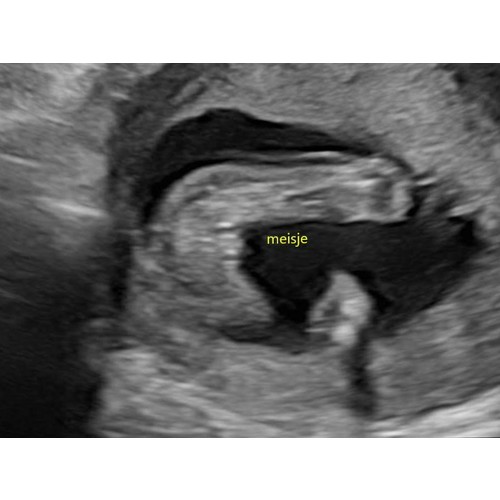

Duidelijk een jongen. Ik krijg een meisje en daarbij zag je duidelijk de hamburger, hier zie je echt balletjes.